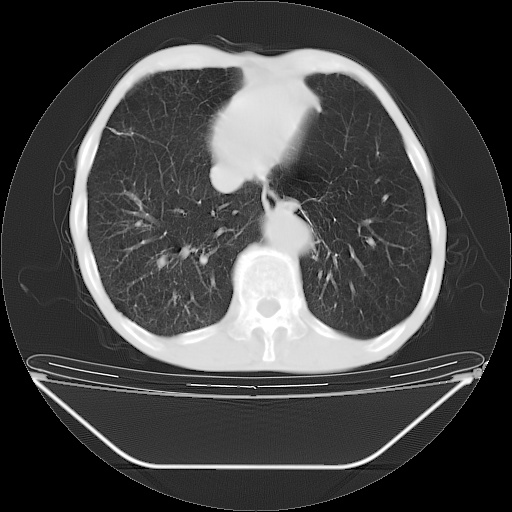

以下是引用zsl6918在2008-8-25 21:55:00的发言:[br]符合右肺周围性肺癌并肺内转移,左肺结核球。双肺肺气肿。腰椎附件转移。

以下是引用随光逐影在2008-8-25 22:03:00的发言:[br]1)考虑右肺下叶周围性肺癌并肺内转移,腰椎附件转移。2)左上肺结核(结核球形成)。3)双肺肺气肿(多发肺大泡形成)。4)双肺门区及纵隔内多发淋巴结钙化。